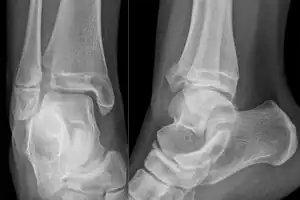

On X-rays, there can be a fracture of the medial malleolus, the lateral malleolus, and/or of the anterior/posterior margin of the distal tibia. The posterior margin (known as the posterior malleolus) is much more frequently injured than the anterior aspect of the distal tibia. If both the lateral and medial malleoli are broken, this is called a bimalleolar fracture (some of them are called Pott's fractures). If the posterior malleolus is also fractured, this is called a trimalleolar fracture.